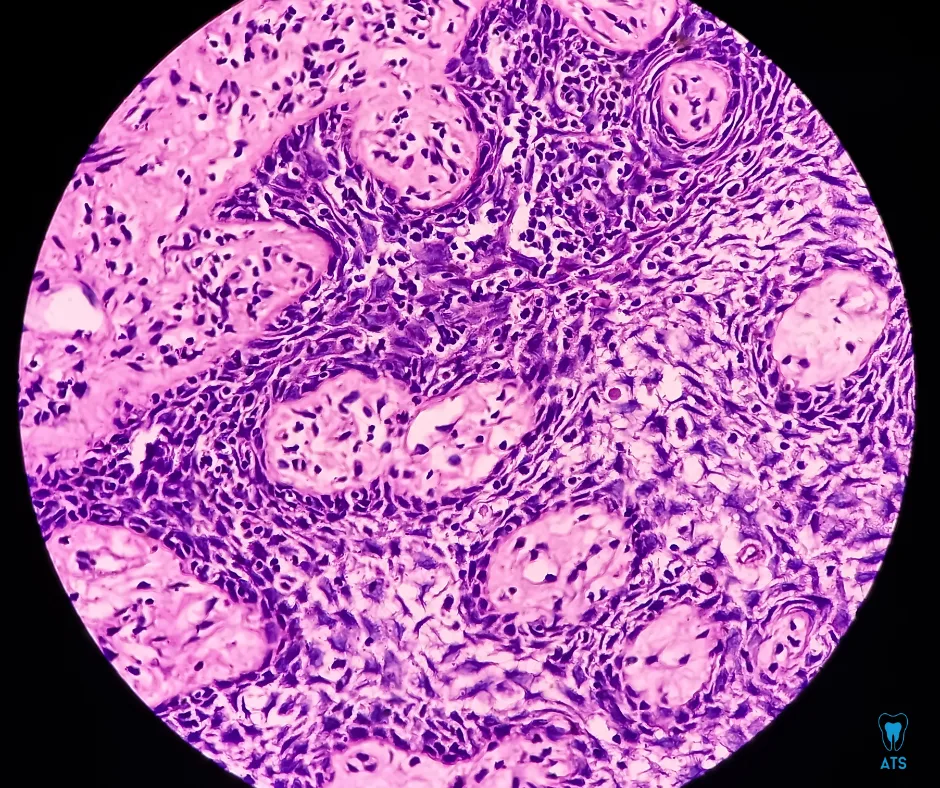

At ATS Dental Clinic, our Oral Pathology services focus on the early detection, diagnosis, and management of oral diseases—from simple ulcers to complex precancerous and cancerous lesions. With advanced diagnostic techniques and years of expertise, we ensure accurate diagnosis and personalized treatment plans.